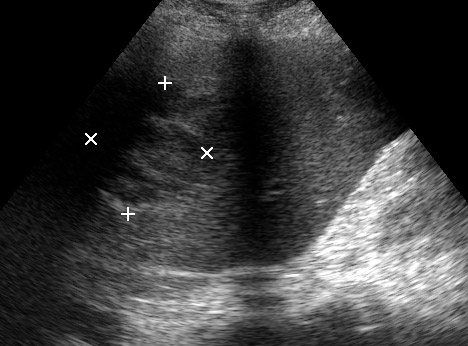

Типичная картина ##1-4:

Гипоэхогенное неоднородное округлое образование, окруженное эхогенным "демаркационным валом"

измененной паренхимы печени.

Лечение:

Абсцессы, которые можем задренировать - дренируем.

abscdrenaige.jpg

Те, которые не можем задренировать - проводим АБ-терапию.